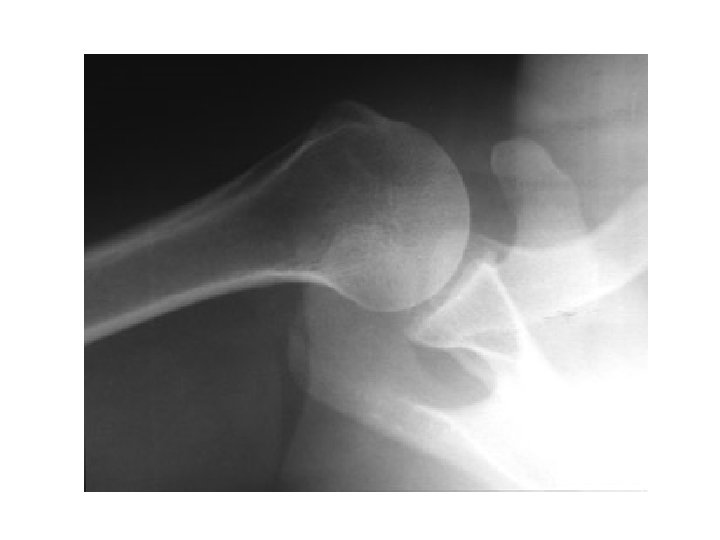

2. Axillary

Transcapular or “Y” View